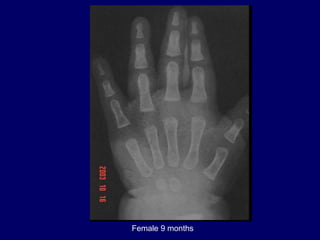

Female 9 months